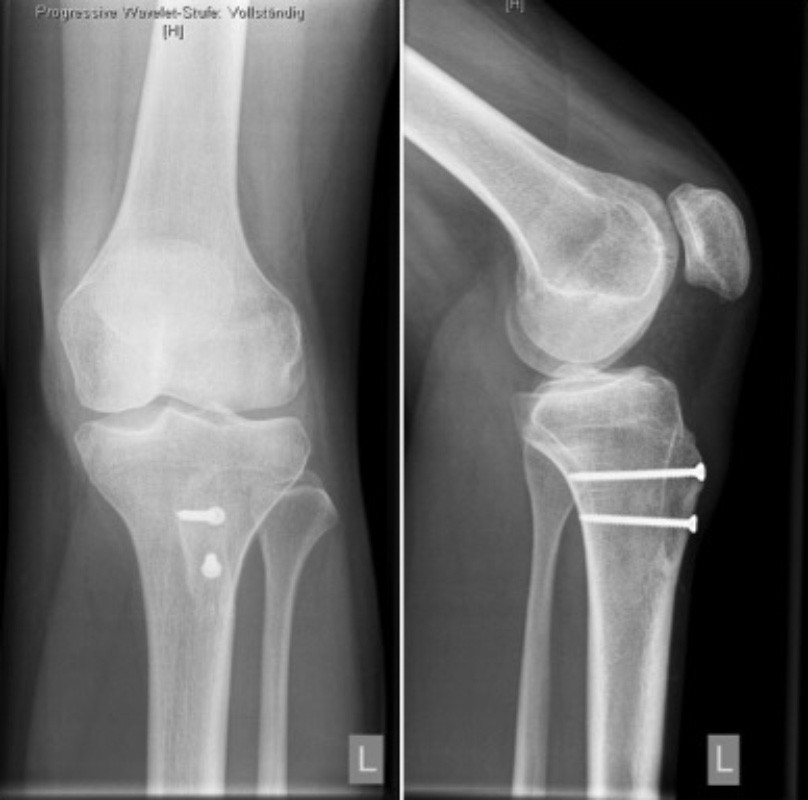

Hierfür wird der Sehnenansatz mit einem anhaftenden Knochstück vom Unterschenkelknochen gelöst und nach innenseitig verschoben bis die ausgemessene Fehlstellung korrigiert ist. Gleichzeitig kann bei diesem Eingriff auch die Höhe der Kniescheibe im Verhältnis zum Gelenkspalt korrigiert werden, indem der Sehnenansatz weiter in Richtung Fuß verschoben wird. Schließlich wird das abgelöste Knochenstück mittels 2- 3 Schrauben in der neuen Position fixiert. Hierdurch kommt es zu einer sicheren Ausheilung. Dieser Eingriff wird in der Regel mit dem Ersatz des MPFLs kombiniert.

Nach dem Eingriff sollte das Bein 6 Wochen lediglich mit 20 kg belastet werden. Eine Beugung des Kniegelenkes ist in der Regel in den ersten 3 Wochen bis 60°, und für weitere 3 Wochen bis 90° möglich.